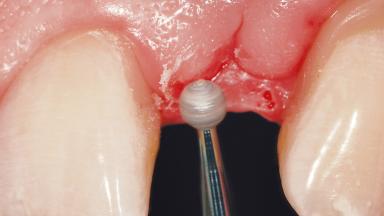

Treatment of Peri-Implant Mucositis at a Zirconia Implant

Frank Schwarz, Ausra Ramanauskaite

Recent clinical studies, most with short-to-medium term observation periods, have reported on the favorable clinical performance of zirconia implants in terms of survival rates, clinical, and radiographic outcomes (Roehling and coworkers 2016; Roehling and coworkers 2017; Rodriguez and coworkers 2018; Lorenz and coworkers 2019). Nonetheless, a rather high incidence of peri-implant disease at zirconia implants (39% of implants) was noted throughout a two-year period, highlighting the need for treatment protocols of peri-implant diseases at zirconia implants (Becker and coworkers 2017).